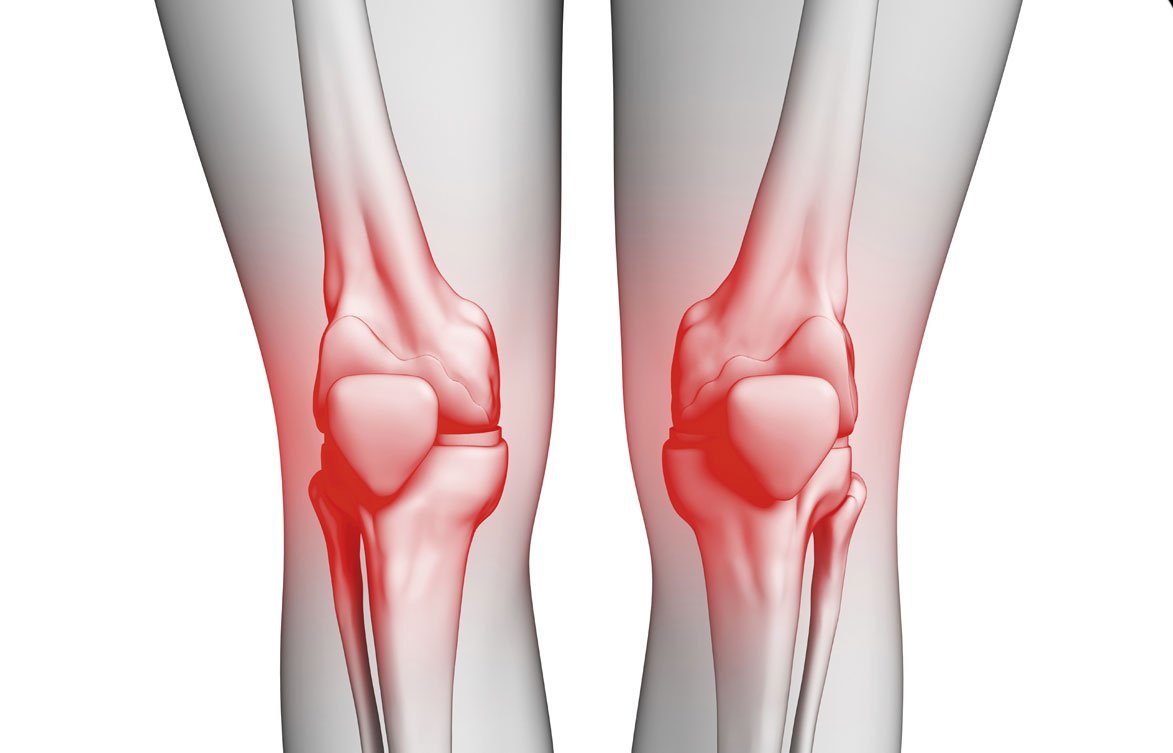

خشونة الركبة تُعد من المشكلات الصحية الشائعة التي تؤثر على جودة حياة الإنسان، خاصةً مع التقدم في العمر أو بسبب عوامل أخرى متعلقة بأسلوب الحياة أو الإصابات. تُعرف خشونة الركبة بأنها تآكل أو تدهور في الغضاريف التي تغطي مفصل الركبة، مما يؤدي إلى احتكاك العظام ببعضها البعض، وهو ما يسبب ألمًا وتيبسًا وصعوبة في الحركة. في هذا المقال، نستعرض أسباب خشونة الركبة بشكل شامل، ونوضح كيف يمكن الوقاية منها وعلاجها بطرق غير جراحية، تحت إشراف الأستاذ الدكتور هشام العزازي، أحد أبرز المتخصصين في علاج الألم والعلاج التداخلي المحدود.

ما هي أعراض خشونة الركبة؟

بعد أن عرفنا أسباب خشونة الركبة، من المهم أن نُسلّط الضوء على الأعراض التي قد تشير إلى وجود هذه الحالة:

- ألم مزمن في الركبة يزداد مع المشي أو الوقوف.

- تيبس في المفصل خصوصًا في الصباح.

- صوت “طقطقة” عند تحريك الركبة.

- تورم بسيط حول المفصل.

- صعوبة في صعود أو نزول السلالم.